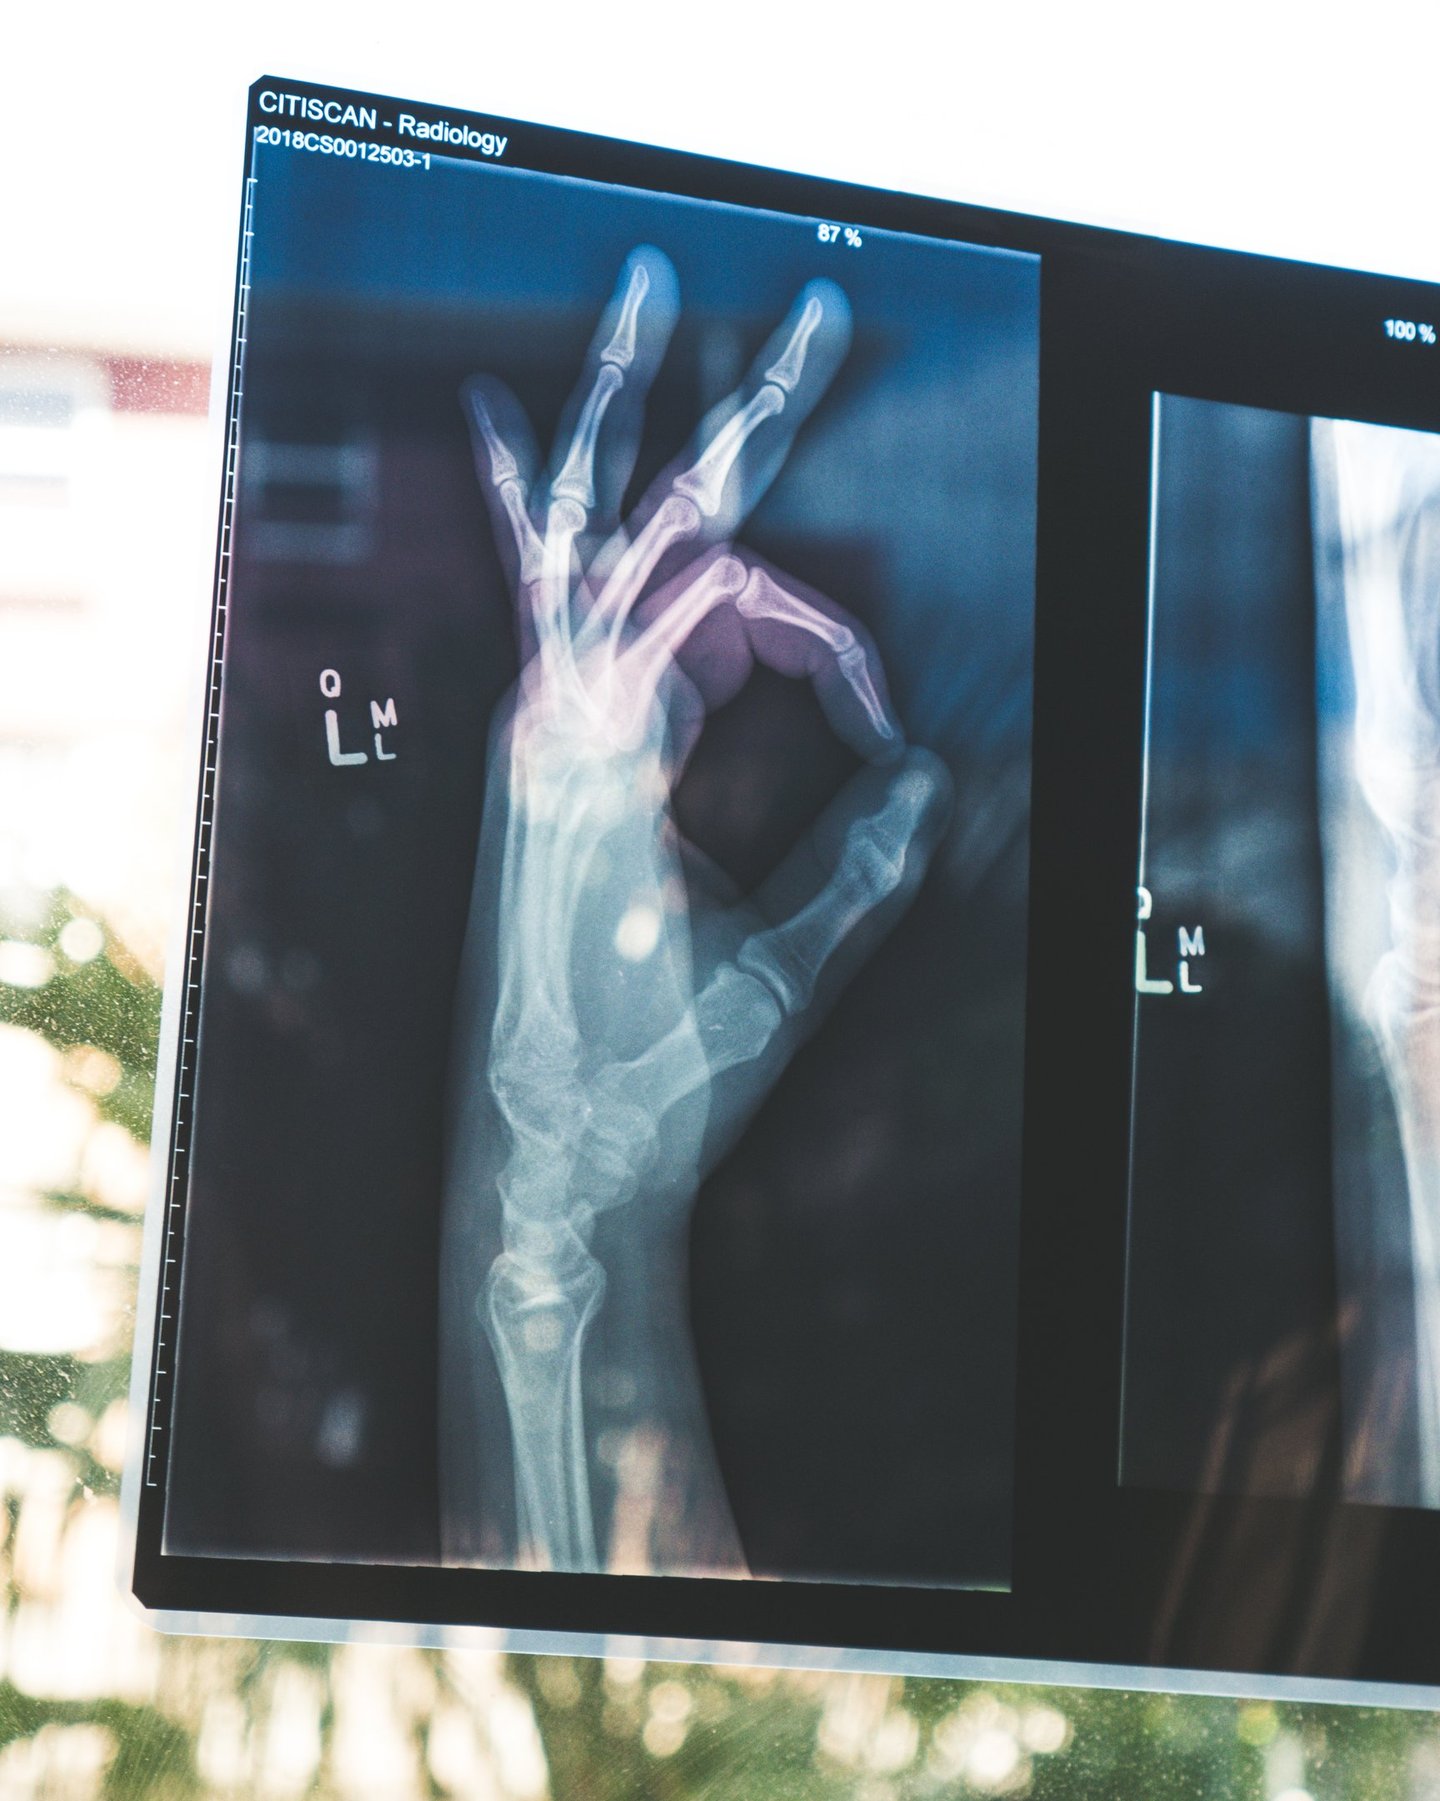

Photo by Wendy Scofield on Unsplash